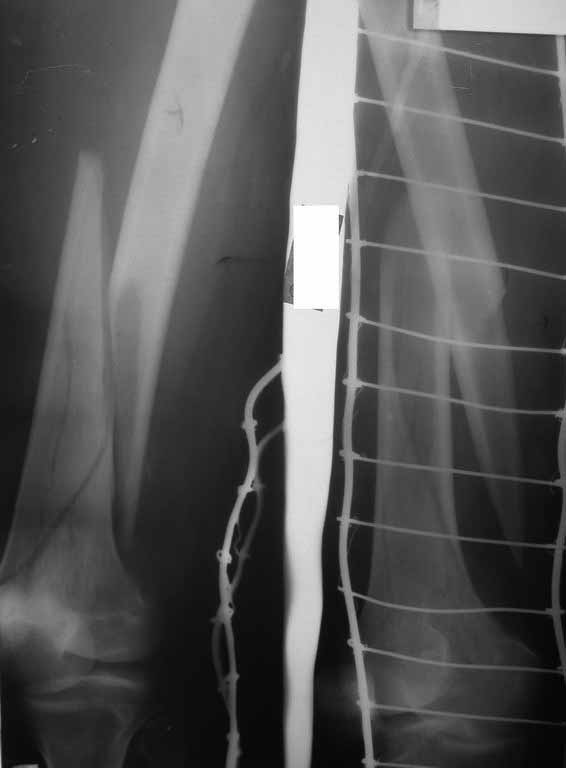

Представляю вам один из наших недавних случаев выполнения малоинвазивного остеосинтеза бедренной кости обычной пластиной 95 градусов.  Длина восстановлена с помощью дистрактора (по сути это основная и б(о)льшая часть репозиции). Произведено два небольших доступа, проведена спица направитель. Рентген-контроль для подтверждения достаточной длины/оси(ЭОП использовался в другой операционной). Создание тунеля обратной стороной фиксатора. Поворот фиксатора, введение клинка по спице. Фиксация проксимального и дистального концов пластины.

Вложение не в текстовом формате было извлечено…

Имя     : 2Xpre3.JPG

Тип     : image/jpg

Размер  : 14364 байтов

Описание: отсутствует

Url     : http://weborto.net:8080/pipermail/ortho/attachments/20110902/aa3367e1/attachment-0008.jpg